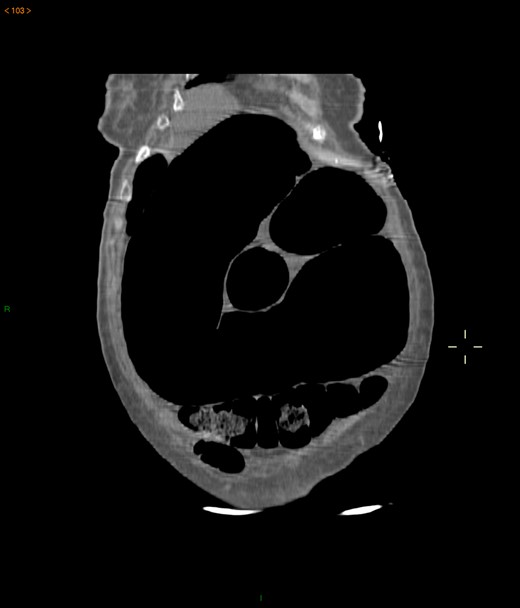

Case 1: A 40-year-old men, without previous abdominal surgery or history of abdominal trauma or peritoneal infections was admitted to the emergency department with generalized abdominal pain, nausea and vomiting. Physical exam revealed a distended abdomen, with pain in the epigastrium without tenderness. Laboratory investigation on admission was normal. Abdominal X-ray revealed a marked sigmoid colon distension suggestive of a colonic volvulus. A colonoscopy was conducted and revealed necrosis of the colon sigmoid apparently form a colonic volvulus. Abdominal-pelvic computerized tomography(CT) was conducted and a colonic volvulus associated with a transmesocolic hernia with transmural necrosis of the colon sigmoid was identified (Fig. 1). The patient was proposed to laparotomy during which a volvulus of sigmoid colon with transmural necrosis in a strangulated descendent transmesocolic hernia was identified. A Hartmann procedure was conducted and the patient was discharged at sixth post-operative day. At 2 year follow-up consultation, the patient remained free of complains, with the intestinal transit re-established.

Abdominal-pelvic CT—coronal plane: colonic volvulus associated with a transmesocolic hernia with transmural necrosis of the colon sigmoid.